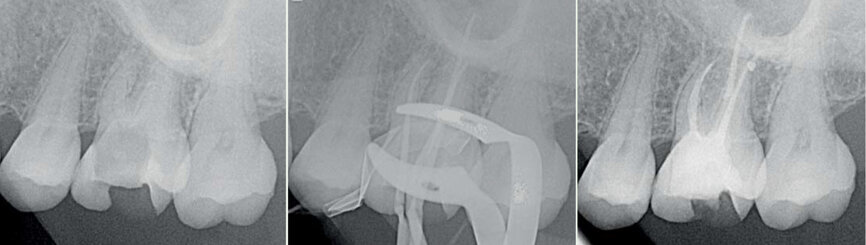

Figs. 1 : Cas clinique réalisé avec le système Genius (c Dr Carlos Spironell Ramos).

Si l’Orifice Shaper s’emploie de manière classique en rotation continue, les limes suivantes s’utilisent en réciprocité avec des paramètres optimisés pour une meilleure sécurité : 90° dans le sens horaire, 30° dans le sens anti-horaire. Une fois la longueur de travail atteinte, ces instruments sont utilisés pendant quelques secondes en rotation continue conventionnelle, pour mieux éliminer les débris dentinaires. La réciprocité permet de préparer les canaux avec seulement trois instruments. L’argument invoque par le fabricant pour justifier le choix des limes a 4% est une moindre mutilation des parois canalaires à mi-hauteur de la racine, réduisant les risques de fragilisation ou de perforation latérale, et l’élargissement du tiers apical à un diamètre plus compatible avec une bonne désinfection du canal. En outre, une conicité plus petite offre plus de flexibilité et plus de résistance à la fatigue cyclique. La progression en réciprocité est très rassurante car on ne ressent aucune aspiration de l’instrument vers l’apex, mais son mouvement un peu saccadé peut être déstabilisant au premier abord. La conicité réduite permet d’atteindre très rapidement la longueur de travail avec la lime n° 25. Ensuite, les limes n° 30 (pour les canaux courbes et étroits) ou 35 (pour les canaux courbes) n’ont que peu d’effort à fournir pour terminer la préparation, les plus grosses étant réservées aux dents monoradiculées (n° 40 et 50). N’importe quelle méthode d’obturation peut être utilisée avec ce type de préparation, à condition d’employer des pointes de gutta de conicité .04 (Tableau n °1).

Le système Genius est donc un ensemble limes-moteur-contre-angle endodontique qui propose une approche et des concepts différents à ceux généralement enseignés, donc en opposition. Mais, ce système est simple, alliant la réciprocité et la rotation continue. De nombreux cas ont été réalisés et montrent que ce système endodontique est fiable et a réellement sa place dans la pratique quotidienne. L’essayer c’est l’adopter (Figs.8–11).